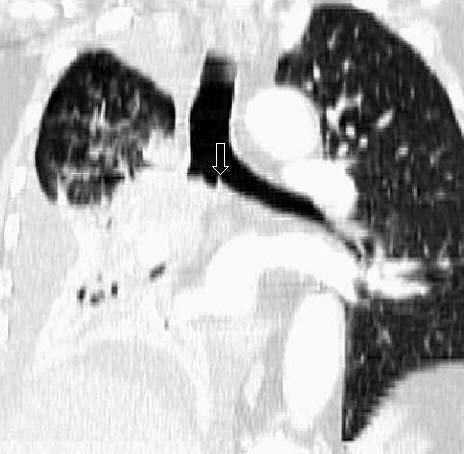

La detección de nódulos pulmonares diferentes del tumor primario es muy superior cuando el estudio está hecho con un equipo de TCMD, debido al menor espesor de corte e intervalo de reconstrucción, lo que confiere una mayor resolución espacial. Esto permite hacer reconstrucciones de proyección de máxima intensidad (MIP) que incrementan significativamente la detección de nódulos, fundamentalmente los de localización central (fig. 13)18.

Fig. 13.--Metástasis pulmonares. (A) Atelectasia del lóbulo inferior izquierdo secundaria a tumor central con nódulo pulmonar contralateral (flecha). (B) Proyección de máxima intensidad (MIP) de 15 mm al mismo nivel que muestra más nódulos (flechas).